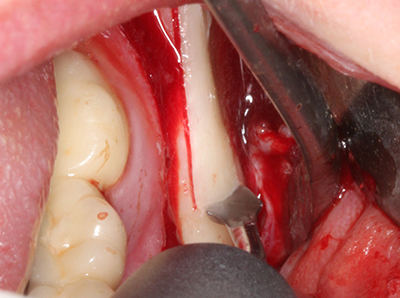

Fig. 18: Preparation of a cortical cover with the piezo bone saw (Piezomed, W&H).

Fig. 19: Surgical site after neurolysis and removal of osteoma.

Fig. 20: The removed bone cover is re-adapted and fixed with an osteosynthesis screw (KLS Martin, Tuttlingen).